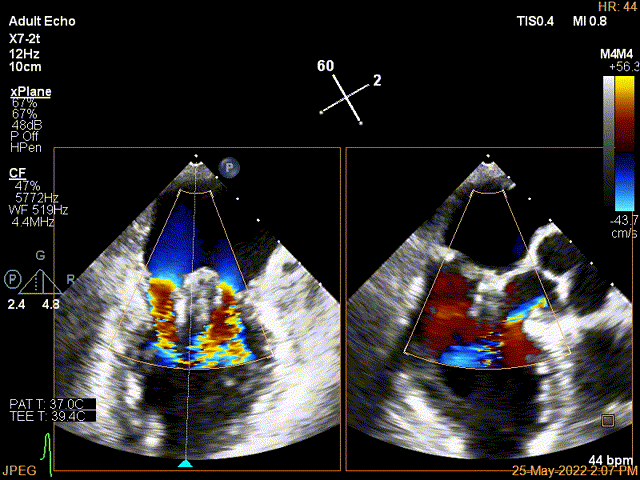

图4: 成功夹合二尖瓣P1P2区,超声显示P2区外侧脱垂

图5: 成功夹合二尖瓣A2P2区残余脱垂。整体反流量降至微量反流